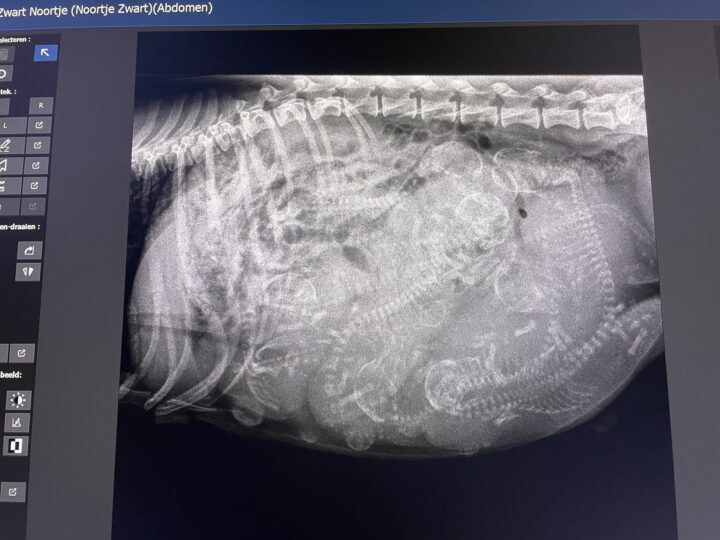

Hier de eerste foto’s van de puppy’s van onze knappe Bl & Tn reu Tomland Teckel Remy PUZZLE voor de insiders; en de eerste uitverkoren Choc & Tn dame is onze Jump For Joy From Black Palace, beter bekend als NOOR (tje) !!